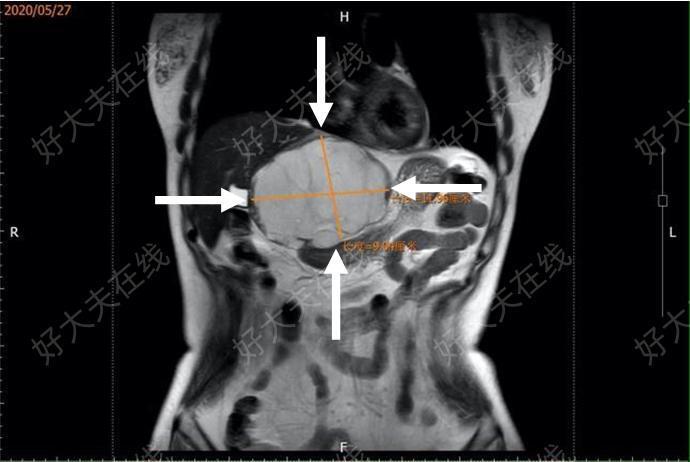

治療前 X女士2007年體檢時(shí)發(fā)現(xiàn)患有肝血管瘤(大小3-4 cm);由于肝血管瘤是一種良性腫瘤、生長(zhǎng)緩慢,醫(yī)生囑咐X女士無(wú)需處理、隨訪即可。如醫(yī)生所言,之后隨訪中腫瘤生長(zhǎng)緩慢,X女士便與這枚良性腫瘤和平共處,期間并無(wú)不適。 2018年5月的一天打破了這種寧?kù)o。X女士復(fù)查時(shí)發(fā)現(xiàn)這個(gè)“老朋友”已經(jīng)長(zhǎng)到了10 cm以上,較上次復(fù)查增大了2-3 cm,該院外科醫(yī)生提醒X女士:太大的血管瘤有破裂風(fēng)險(xiǎn)、需要手術(shù)。X女士第一次感覺(jué)到這個(gè)“老朋友”的威脅性。出于謹(jǐn)慎,X女士又咨詢(xún)了幾位外科醫(yī)生,得到的回復(fù)卻十分不同:有人建議手術(shù),有人說(shuō)手術(shù)風(fēng)險(xiǎn)過(guò)大、不建議手術(shù)。這種境況讓X女士慌了神,到底能不能手術(shù)呢?不手術(shù)的話會(huì)不會(huì)有生命危險(xiǎn)呢?手術(shù)的創(chuàng)傷大、風(fēng)險(xiǎn)大,怎么辦?X女士想要治療,可外科切除手術(shù)創(chuàng)傷太大,又不想冒險(xiǎn),就這樣一直在兩難的尷尬境地里煎熬著。 轉(zhuǎn)瞬間到了2020年,X女士從親朋好友處聽(tīng)說(shuō)上海市第十人民醫(yī)院的超聲介入科余松遠(yuǎn)主任擅長(zhǎng)肝血管瘤的微創(chuàng)治療,打聽(tīng)到余主任在介入手術(shù)的口碑非常好。于是找到了余主任,溝通中X女士了解到:這顆巨大的肝血管瘤是她近1年來(lái)持續(xù)腹脹的罪魁禍?zhǔn)?,像一顆定時(shí)炸彈,施行外科切除手術(shù)的創(chuàng)傷確實(shí)會(huì)比較大,最佳的治療方案是微創(chuàng)微波消融治療:一根針搞定一顆大腫瘤,創(chuàng)傷小、風(fēng)險(xiǎn)小、恢復(fù)快。于是果斷住進(jìn)了超聲介入病房,開(kāi)始這場(chǎng)“拆彈”手術(shù)。 圖1 術(shù)前MRT1加權(quán)冠狀面肝左葉被巨大血管瘤占據(jù),壓迫胃與?二指腸,腫瘤大小12.8×9 cm 圖2 術(shù)后第4天MRT1加權(quán)冠狀面腫瘤明顯萎縮,周?chē)鞴賶浩冉獬?,術(shù)后腫瘤?小8.9×5.5 cm 入院第二天X女士做了上腹部MR(如圖1),經(jīng)過(guò)系統(tǒng)評(píng)估與討論,該院超聲介入團(tuán)隊(duì)針對(duì)這枚占據(jù)了整個(gè)肝左葉的巨大血管瘤,制定了最佳治療方案:聯(lián)合肝外科共同施行腹腔鏡引導(dǎo)下微波消融術(shù)。 2020年5月28日11點(diǎn)30分,這項(xiàng)肝巨大血管瘤“私人定制手術(shù)”在手術(shù)室開(kāi)始了。肝外科孟主任、超聲介入科余主任的強(qiáng)強(qiáng)聯(lián)合:腹腔鏡直視下,將微波消融針穿刺入瘤體內(nèi)開(kāi)始序貫消融,瘤體的消融區(qū)就像氣球放氣了一樣萎縮了下來(lái)。該手術(shù)在1點(diǎn)31分順利結(jié)束,歷時(shí)2小時(shí),術(shù)中出血量控制在20 ml以?xún)?nèi)。在場(chǎng)的醫(yī)務(wù)人員都不禁感嘆:原來(lái)傳說(shuō)中的微波消融對(duì)血管瘤治療效果這么好! 肝巨大血管瘤學(xué)科聯(lián)合私人訂制 手術(shù)流程 ①腹腔鏡:肝?管瘤占據(jù)整個(gè)上腹部腹腔 ②在瘤體周邊墊紗布?jí)K保護(hù)周邊臟器 ③腹腔鏡操作桿撬起瘤體! ④ 腹腔鏡直視下開(kāi)始微波消融 ⑤ 肝外科-超聲介?多學(xué)科聯(lián)合?術(shù)現(xiàn)場(chǎng) ⑥ 消融后瘤體整體萎縮 至此,X女士體內(nèi)這枚巨大的“定時(shí)炸彈”大部分拆除完畢。術(shù)后第2天,X女士便下床活動(dòng),第3天已行動(dòng)自如了,以往上腹部脹痛和壓迫感消失,為確認(rèn)這次多學(xué)科聯(lián)合新式手術(shù)的治療效果,X女士于本院復(fù)查了MR:顯示術(shù)后肝左葉腫瘤區(qū)域已完全無(wú)增強(qiáng)。術(shù)后第4天,X女士基本恢復(fù),順利出院歸家。出院前感謝余主任、孟主任及所有相關(guān)的醫(yī)療工作人員對(duì)她的關(guān)照! 術(shù)前 增強(qiáng)MR橫斷面顯示腫瘤周邊結(jié)節(jié)狀與環(huán)狀增強(qiáng),逐漸向內(nèi)填充 術(shù)后 增強(qiáng) MR 橫斷面顯示腫瘤無(wú)增強(qiáng) 余松遠(yuǎn)主任答廣大肝血管瘤患者問(wèn): 1 得了肝血管有沒(méi)有危險(xiǎn)? 答: 肝血管瘤是一種常見(jiàn)的良性腫瘤,一般來(lái)說(shuō)生長(zhǎng)緩慢。早期可無(wú)癥狀,隨著腫瘤增大可壓迫周?chē)K器出現(xiàn)相應(yīng)癥狀,特別是大于10 cm的巨大血管瘤,可出現(xiàn)肝功能異常等,有破裂出血的風(fēng)險(xiǎn)。 2 肝血管瘤什么情況下需要治療呢? 答: 當(dāng)腫瘤較?。Γ?0;5 cm并無(wú)特殊癥狀時(shí),一般無(wú)需處理。當(dāng)腫瘤>5 cm以后可選擇手術(shù)切除 或者微波消融術(shù)對(duì)腫瘤進(jìn)行干預(yù)。血管瘤做微創(chuàng)消融治療的最佳時(shí)機(jī)是:瘤體最大徑為5-10 cm之間。 3 我是肝巨大血管瘤患者,當(dāng)?shù)蒯t(yī)院醫(yī)生認(rèn)為血管瘤破裂的機(jī)率比較小、不建議手術(shù)。這個(gè)觀點(diǎn)您怎么看? 答: 臨床上認(rèn)為肝巨大血管瘤破裂的病人少,實(shí)際是對(duì)肝巨大血管瘤破裂機(jī)率的低估。我? 邊就發(fā)生過(guò)一例巨大血管瘤病人,之前血管瘤還較小時(shí),看了很多醫(yī)生都說(shuō)不用治療,多年以后,血管瘤長(zhǎng)到20多公分,再找多家大醫(yī)院醫(yī)生都認(rèn)為手術(shù)風(fēng)險(xiǎn)極高而拒絕收治,患者無(wú)奈地回家盡量不活動(dòng),但還是在一次不大的顛簸后,血管瘤破裂出血,猶如水庫(kù)大壩潰堤,從有癥狀到死亡只有20幾分鐘,都沒(méi)來(lái)得及送上救護(hù)車(chē)。因而,很多巨大血管瘤破裂死亡的病人其實(shí)并沒(méi)送到大醫(yī)院臨床治療,因而給很多臨床醫(yī)生一種“安全、機(jī)率小”的錯(cuò)覺(jué)。 4 對(duì)于肝巨大血管瘤,微創(chuàng)消融術(shù)相對(duì)于傳統(tǒng)手術(shù)的優(yōu)勢(shì)在哪里? 答: 肝血管瘤是良性病變,瘤體較小時(shí)用傳統(tǒng)的手術(shù)方式切除血管瘤瘤體及其周?chē)母稳~組織,有一種因創(chuàng)傷大,風(fēng)險(xiǎn)高而得不償失的感覺(jué);當(dāng)瘤體太大時(shí)不管是外科切除、介入栓塞和經(jīng)皮消融治療的風(fēng)險(xiǎn)都極大,術(shù)后肝功能會(huì)受到相應(yīng) 治療后 治療后365天 復(fù)查左肝外生性巨大血管瘤縮小至2x3㎝瘢痕。肝臟外形正常,對(duì)胃腸的壓迫消除了。 治療后30天 患者術(shù)后隨訪,腹脹明顯緩解,說(shuō)明腫瘤縮小后解除了腫瘤對(duì)胃腸的壓迫,術(shù)前測(cè)算體積約6000ml,術(shù)后測(cè)算腫瘤體積約220ml。